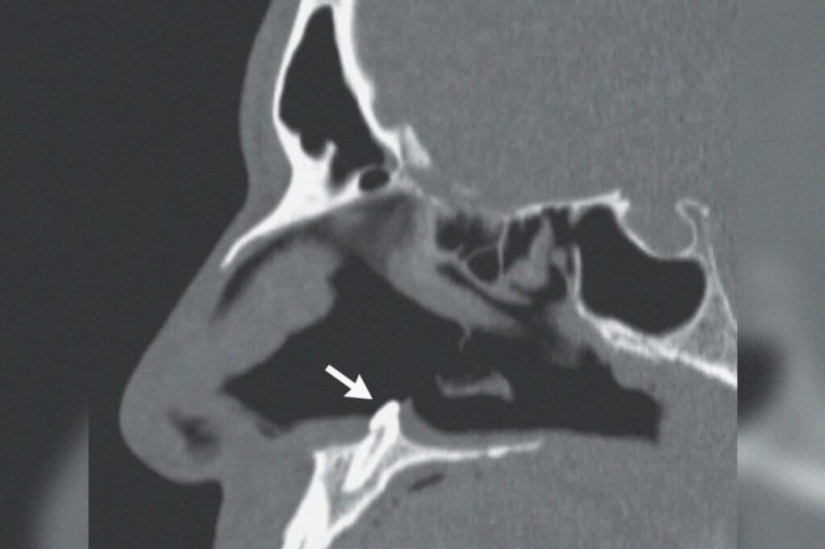

Por Pictolic https://mail.pictolic.com/es/article/en-los-eeuu-los-cirujanos-extirparon-un-diente-que-creci-en-la-nariz-de-un-hombre.htmlA veces el cuerpo humano arroja sorpresas a los médicos, obligándolos a romperse la cabeza a fondo. Los cirujanos del Complejo Médico Mount Sinai en Nueva York recientemente tuvieron que extirpar un diente de un hombre de 38 años que le había crecido justo en la nariz. No era una nimiedad, sino un colmillo real con una longitud de 14 mm!

El paciente fue a los médicos quejándose de dificultad para respirar. Según él, los problemas comenzaron hace varios años, pero ahora se han vuelto simplemente insoportables. Un examen superficial reveló una curvatura del tabique nasal en el paciente, así como un cierto sello en la profundidad del pasaje nasal.

La tomografía lo puso todo en su lugar. El llamado diente ectópico resultó ser un sello incomprensible. Este es el nombre de los dientes que han crecido en lugares inadecuados para ellos. Este fenómeno raro, pero no excepcional, puede estar asociado con el crecimiento de los dientes de leche. A veces, tal diente no se cae, sino que permanece en algún lugar de los tejidos.